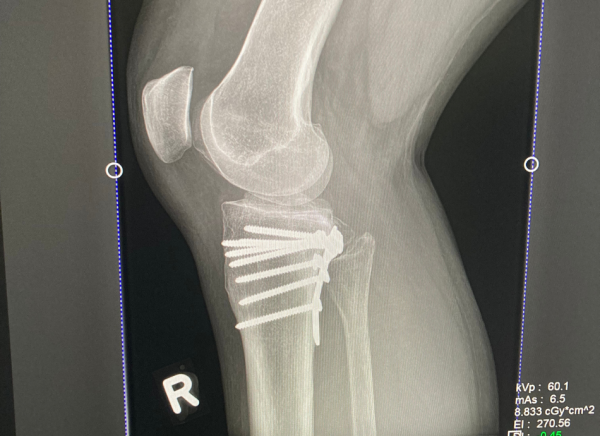

The most common way to diagnose a fracture is by an x-ray. An x-ray shows the type of fracture and its location within your bone. Sometimes an MRI or a CT scan may be needed.

- A more severe fracture may need surgery to insert pins, plates or screws to hold your bone in place.

Treatment aims to move your broken bone back to its original position (if it is displaced) and then hold it in place to allow healing. The process of moving your bone back to its original position is called reduction and holding your bone together (stopping it from moving) is called immobilisation.

Image credit: Healthify He Puna Waiora, NZ, 2023